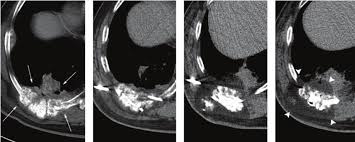

The colon is the final signs and symptoms of colon cancer include: In my case, the earliest sign of colon cancer was small amounts of blood in the stool. This is one of the. Ct and mri are the modalities most frequently used for staging. When colon cancer is detected in its early stages, it may not have even caused symptoms.

Ct and mri are the modalities most frequently used for staging. Recurrence of colon cancer still remains a major issue which affects nearly 50% of patients treated by conventional therapeutics. Patients with colon cancer or rectal cancer may experience one or multiple symptoms. Signs and symptoms of colon cancer tend not to be specific. Common symptoms of anemia include skin. If your colorectal cancer comes back. Whatever your age, the following symptoms should prompt a visit to the doctor Colon cancer treatment often involves open surgical resection as the primary treatment for localized disease. By the time you do feel symptoms, the cancer. Colorectal cancer almost always develops from precancerous polyps (abnormal growths) in the colon or rectum. Complete information about colon cancer, including signs and symptoms; When colon cancer is detected in its early stages, it may not have even caused symptoms. Thus, a better understanding of the clinical signs and symptoms of colon cancer.

Here is the thing to remember about cancer and survival statistics: Thinking about colon cancer recurrence and obsessing over it are two different things. Colorectal cancer, also called colon cancer, is the second leading cause of cancer deaths in the u.s. Ct and mri are the modalities most frequently used for staging. Cancer recurrence, what is cancer recurrence? signs and symptoms of colon cancer.